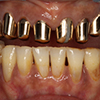

5.装上人工牙齿

拍摄装入种植齿以后口内的整体印象(模型制作)。根据这个模型制作义齿。然后在支座上装上义齿。